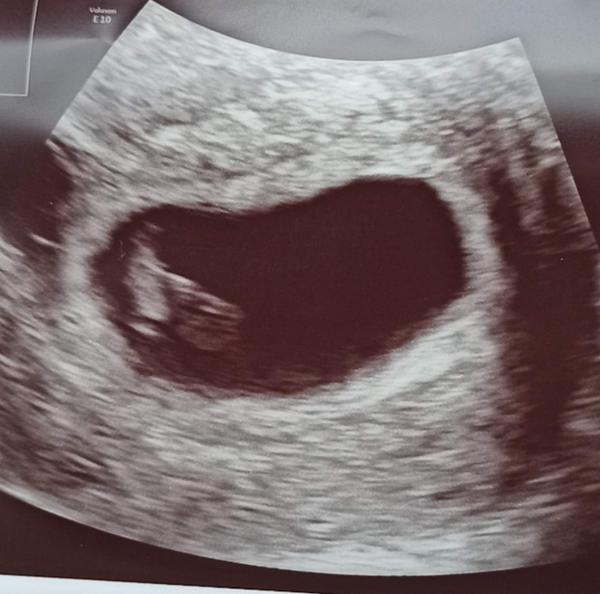

@bambulka711 Toto je moje 7+1tt, takze 7+3tt uz urcite bude nieco vidiet 🙂

@bambulka711 tak veď liečbu nasadenú máš, tak asi viac dr neskontroluje maximálne či je to vnútromaternicové. Mne bolo vidieť plod s akciou 6+3tt. Týždeň pred tým ešte nevidela plod iba gestačný vak.